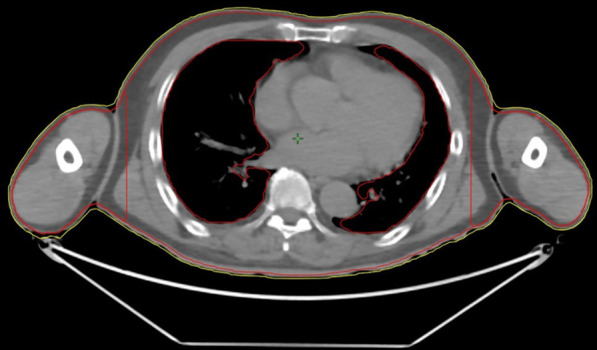

The planning target volume (PTV) included the entire body trimmed to 3 mm below the body. Furthermore, the PTV was divided into two structures, which are the PTV-BODY and the PTV-ARM (Fig. 1). These structures were 14 cm from the center in the left–right direction. The OARs included the lens, lungs, kidneys, and testes, which were excluded from the PTV.

Fig. 1.

The planning target volume (PTV) includes the entire body (yellow segment) trimmed to 3 mm below the body (red segment). Furthermore, the PTV is divided into two structures at 14 cm from the center in left–right direction as PTV-BODY and PTV-ARM